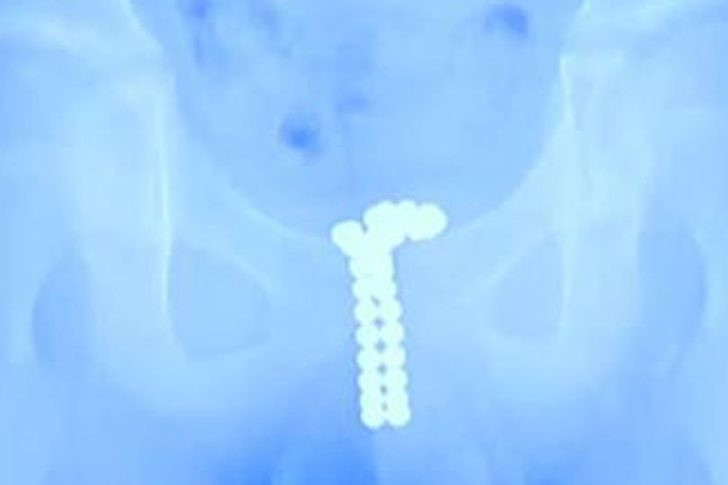

Doğu Çin'in Hubei bölgesinde 12 yaşındaki bir erkek çocuğun penisinde tam 26 mıknatıs topu çıkartıldı. Acı ve kanama ile doktora gelen çocuğun penisine mıknatıs toplarının nasıl girdiğini duyun doktorlar ise şok oldular. Mıknatıs toplarını penisinden 2 saatlik ameliyat sonrasında çıkartıldı. Toplar ise çocuğun penisine bakın nasıl girmiş.

13 Ocak'ta ağrı ve idrara çıkamama şikayetiyle doktora götürülen küçük çocuğa çekilen röntgende ortaya çıkan manzara ise korkunçtu.